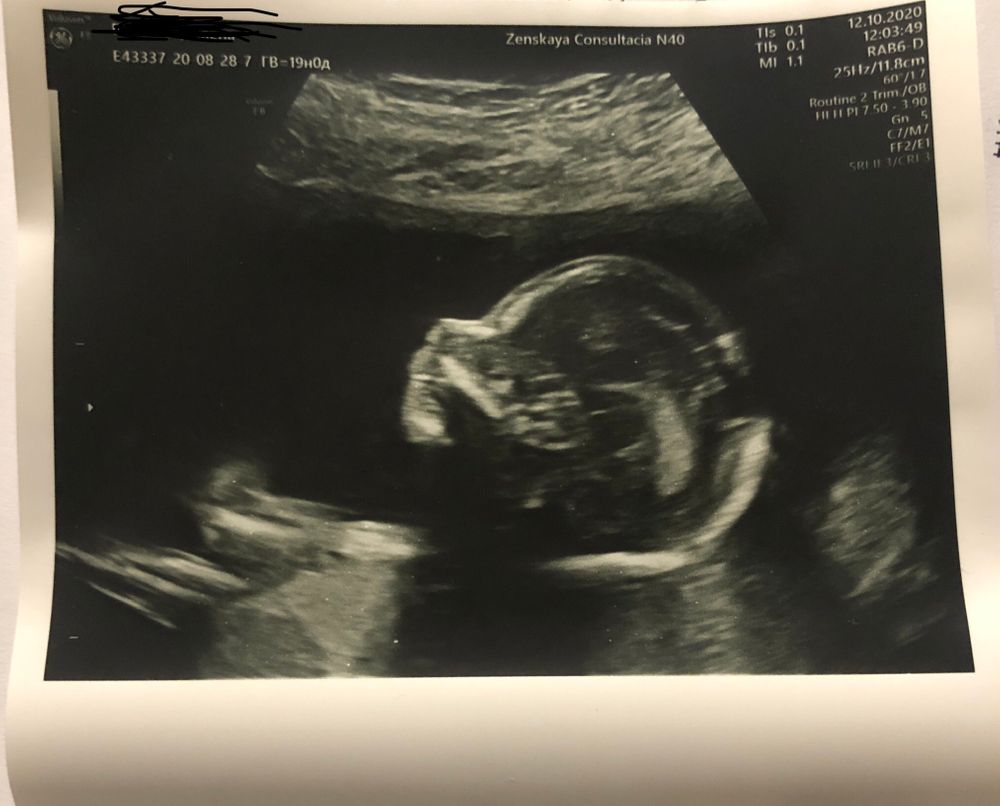

Скрининг 19 Недель Фото

Скрининг 19 Недель Фото 120 фото

13 14 Недель Беременности Фото